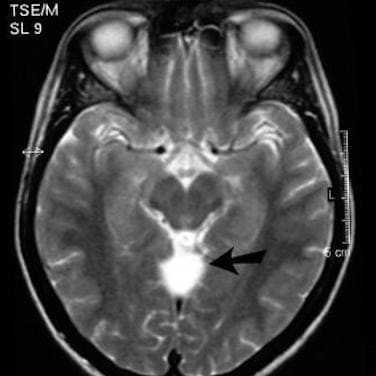

У пациентов детского возраста дифференцированную диагностику кист проводят в отношении пороков развития. Пороки развития обычно проявляются недоразвитием твердой мозговой оболочки. Эта патология в изолированном виде встречается редко, обычно она сочетается с пороками развития головного и спинного мозга. Нередко такая патология у детей сопровождается дефектами черепа или расщеплением дужек позвонков с образованием грыж. В зависимости от содержимого грыжевого мешка врачи выделяют:

- менингоцеле - ТМО + ликвор

- менингоэнцефалоцеле - ТМО + ликвор + мозговая ткань

- энцефалоцистоцеле - ТМО + ликвор + мозговая ткань с частью желудочков системы

- атретическое цефалоцеле - ТМО + ликвор+фиброзная ткань + дегенеративно измененная мозговая ткань глиальная киста.